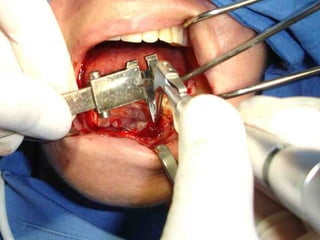

Primer tiempo quirúrgico; Exposición del maxilar para tomar una impresión del

hueso y poder elaborar la estructura implantaria.

Exposición del maxilar para tomar la impresión

Previamente se ha elaborado un portaimpresiones en acrílico de autopolimerización, el

cual será llenado con silicona para obtener el duplicado de la estructura ósea.

En el modelo que se obtuvo en el primer tiempo quirúrgico se elabora en el

laboratorio la estructura que se adptará al maxilar por mecanismo de grapa.

Segundo tiempo quirúrgico para aplicar la estructura.